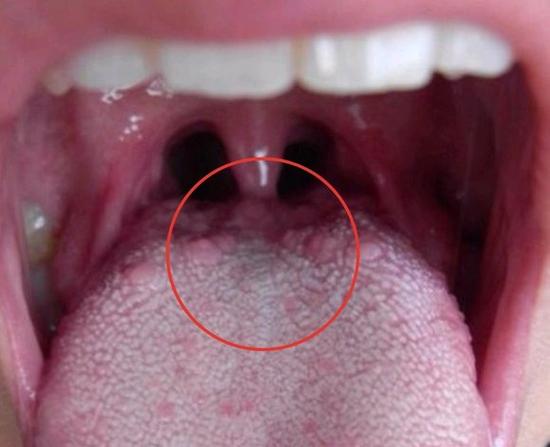

真菌感染:长期使用抗生素、免疫力下降或佩戴假牙者,易感染白色念珠菌,表现为舌面白色斑膜或小泡,撕去斑膜后可见红色糜烂面,伴微痛或灼烧感(俗称“鹅口疮”)。